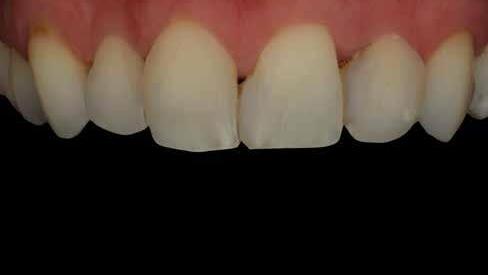

A fogászati kezelések során manapság már nem kizárólag az esztétikai megjelenés helyreállítására törekszünk. Sokszor a kedvezőtlen esztétikai megjelenés hátterében álló okok következményes módon a fogazat funkcionális működését is károsítják, így a kezelések során ezeknek a helyreállításával is foglalkoznunk kell. A különböző funkcionális és esztétikai diszkrepanciák kezelésére számtalan módszer létezik, ám ezen fogászati beavatkozások mindegyikében közös, hogy a kivitelezésük során nagyon szoros együttműködésre van szükség a kezelést végző fogorvos és a munkáját segítő fogtechnikus között. Az alábbi esetbemutatás során egy fiatal hölgypáciens fogazatának héjak alkalmazásával történő esztétikai és funkcionális rehabilitációját szeretnénk ismertetni.

Esetbemutatás

A 19 éves hölgypáciens azzal a kéréssel jelentkezett a rendelőnkbe, hogy szebb fogakat szeretne. Az első konzultáció alkalmával megkérdeztük, hogy mi zavarja leginkább a fogazatának jelenlegi megjelenésében, valamint azt is megbeszéltük vele, hogy milyen végeredmény elérése esetén lenne maradéktalanul elégedett. Ebben az esetben a kezelési célokat az alábbiakban határoztuk meg:

A páciens fogazata esztétikai megjelenésének és funkcionális működésének a lehető legtöbb, saját foganyag megtartása mellett történő helyreállítása (1. és 3. ábra). A lehető legideálisabb esztétikai végeredmény elérése érdekében néhány esetben a fogak alakjának módosítá -

sára is szükség van (2. és 4. ábra).

A kezelés megtervezése során kifejezett jelentősége van annak, hogy jó kommunikáció legyen a páciens, a fogorvos és a fogtechnikus között. A páciens leendő fogazatának természetes megjelenését a kezelésben részt vevő team szakmai felkészültsége, gyakorlati tapasztalata és a kezelés sikerességének irányába történő elkötelezettsége biztosítja. A beavatkozások megkezdése előtt megtörtént a páciens anamnézisének a felvétele, valamint a klinikai kivizsgálását is elvégeztük. Ezt követően lenyomatokat készítettünk a kiindulási állapotról, majd a kiindulási helyzetet extra- és intraorális fotók segítségével is rögzítettük (13. a-c. ábra).